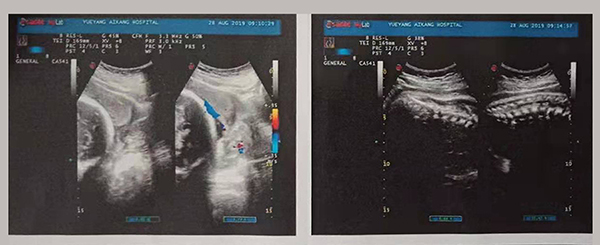

近日,岳陽愛康醫(yī)院產(chǎn)科團隊成功搶救了一名完全性前置胎盤的產(chǎn)婦。完全性前置胎盤是妊娠期的嚴重并發(fā)癥,是分娩期子宮切除的一個重大高危因素之一,是引起孕產(chǎn)婦死亡和圍生兒死亡的重要原因之一。

2019年8月24日,易女士出現(xiàn)陰道流血,在岳陽縣人民醫(yī)院住院,住院期間予以安治、止血,于26日出院。28日早晨6點再次出現(xiàn)陰道流血,量多、顏色鮮紅、三片衛(wèi)生巾均浸透,遂來岳陽愛康醫(yī)院產(chǎn)科。

易女士一進入病房就引起了岳陽愛康醫(yī)院產(chǎn)科主任高君萍的高度重視,考慮到手術的風險大,手術過程復雜,有可能出現(xiàn)新生兒窒息、產(chǎn)婦大出血等危及母嬰生命的并發(fā)癥,甚至切除子宮可能。在檢驗科充分術前配血、血漿的準備及全院MDT(多學科聯(lián)合會診),立即進行手術。

術中,擺在產(chǎn)科團隊面前的第一個嚴峻考驗出現(xiàn)了,整個子宮下段前壁膨隆血管怒張!迅速設計子宮切口,取出胎兒,面臨又一嚴峻的考驗,胎盤大面積植入整個子宮下段前后壁,迅速行雙側(cè)子宮動脈下行支結(jié)扎,迅速人工剝離胎盤以及卵圓鉗鉗夾剩余胎盤組織,植入的胎盤處理干凈后子宮下段前后壁多處肌層缺損伴有大量活動性出血,迅速行子宮下段整形修復縫合止血……不得不說產(chǎn)婦是幸運的,婦產(chǎn)科、手術麻醉科等多科通力合作,經(jīng)過約2小時的手術及搶救止血,術中共計出血1500ml,輸懸浮紅細胞4個單位,終于保得母女平安,并完美的保留了子宮。易女士術后恢復良好,對婦產(chǎn)科的精湛技術贊不絕口!